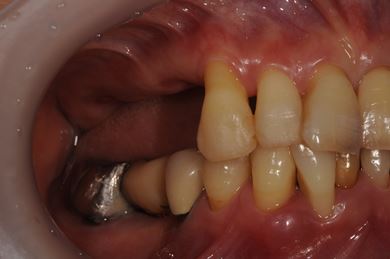

| 性別/年齢 | 女性 / 51歳 | ||||||||||||||||||||||||||||||||

| 主訴 | 他の歯科医院で入れ歯を入れたが、滑舌や味などで不自由を感じている。インプラントは難しいと言われたが、可能かどうかみていただきたい。 | ||||||||||||||||||||||||||||||||

| 治療方針 | サイナスリフトにより上顎洞を拳上し、インプラント治療を可能にする。 | ||||||||||||||||||||||||||||||||

| 治療内容 | インプラント3本(サイナスリフト)、ハイブリッドセラミッククラウン5本 | ||||||||||||||||||||||||||||||||